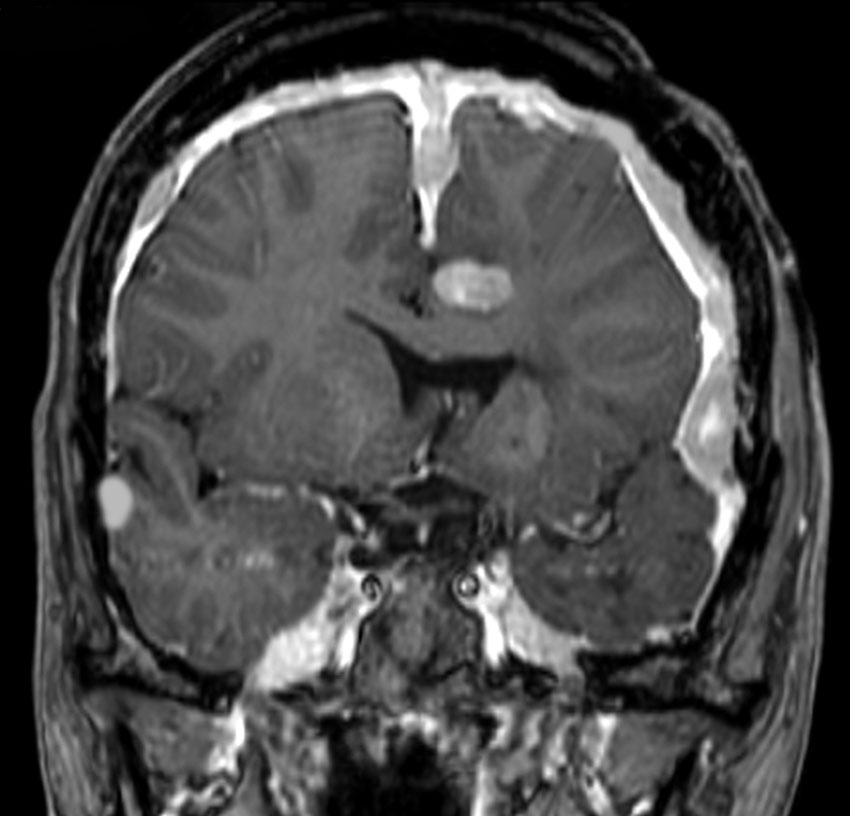

NF-2の多発性髄膜腫

赤の矢印が,両側の聴神経腫瘍です。黄色の矢印は, 多発性の髄膜腫です。蝶形骨縁髄膜腫,穹隆部髄膜腫,大脳鎌髄膜腫,大脳鎌テント接合部髄膜腫などいっぱいあります。これらは基本的に経過観察しますが,とても目立って大きくなるものがあれば摘出します。摘出には注意が必要で,近い将来また手術になるかもしれないので,次回の手術もできるように工夫して開頭手術しなければなりません。でないと,次の手術での合併症が増えます。また一回の開頭で近傍の硬膜や腫瘍を可能な限り摘出してしまうことも大切です。でないと,限りなく手術を繰り返すことになります。